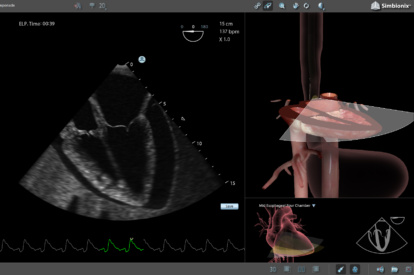

Ultrasound Mentor accelerates the development of basic to advanced technical and cognitive skills, by providing not only the probe manipulation training, but also a didactic environment enabling structured, self-guided learning including step-by-step instructions and educational aids such as 3D anatomical map and probe positioning assistant, all backed up with our progress monitoring tool MentorLearn.

- Advanced diagnostic tools, including Color Doppler, CW, PW, M-mode, and measurements

TEE Module

TEE Emergency Module

Simulation-based teaching of TEE showed a significant improvement in the knowledge, skills, and self-assessment of proficiency of cardiology fellows, as well as a reduction in the amount of time needed to complete the examination. These results should encourage further investigation of clinical performance and patient benefits of TEE simulation training.